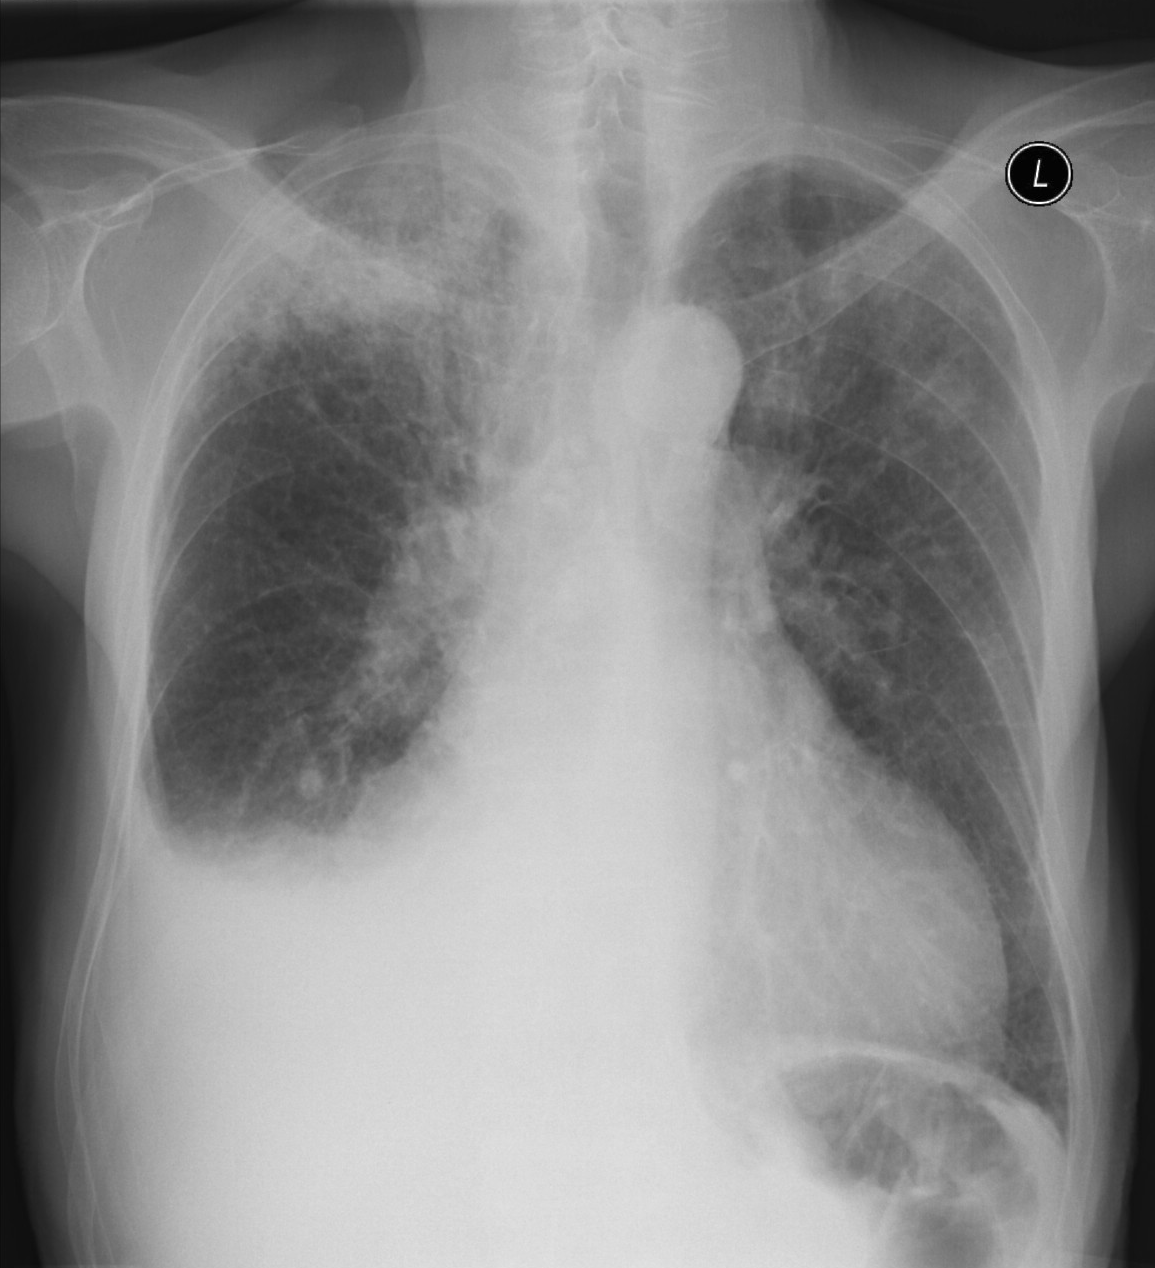

3a: Round shadow: multiple lung metastasis. Chest radiograph (PA)

Image

3b: Multiple lung metastasis, CT lung window (axial, coronal reformat)

3c, coronal reformat

70 year old man, colon tumor.

Radiograph: Bilateral extensive, confluating patchy-nodular shadowing with diffuse reticular pattern. The diaphragm contour is partially blurry bilaterally: lymphangiosis carcinomatosa.

CT: Numerous 1-6 cm round and irregular, lobulated-spiculated contrast enhancing lesions in both lungs, everywhere sporadically.